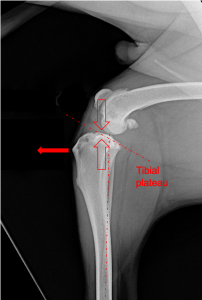

Dogs have a naturally backwards facing joint surface – the tibial plateau. The force of weightbearing causes the femur and tibia to be pushed together (open arrows). Due to the tibial plateau angle, this pushing together forces the tibia forwards (solid arrow). The cranial cruciate ligament resists this force.

A TPLO involves making a curved bone cut (osteotomy) and the rotating the top of the tibia with the joint surface. This aims to eliminate the force pushing the tibia forwards during weightbearing. The osteotomy is stabilised with a bone plate and screws.